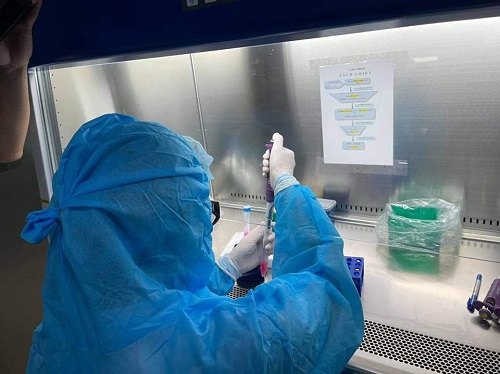

Liên quan đến 02 ca bệnh COVID-19 (F0) là bệnh nhân T.T.N (sinh năm 1974, địa chỉ: Khối 2, phường Vinh Tân, TP Vinh, tỉnh Nghệ An) và bệnh nhân B.V.H (sinh năm 1997, địa chỉ: Khối 2, phường Vinh Tân, TP Vinh, tỉnh Nghệ An) được cơ quan chức năng công bố vào các ngày 25, 26/9/2021